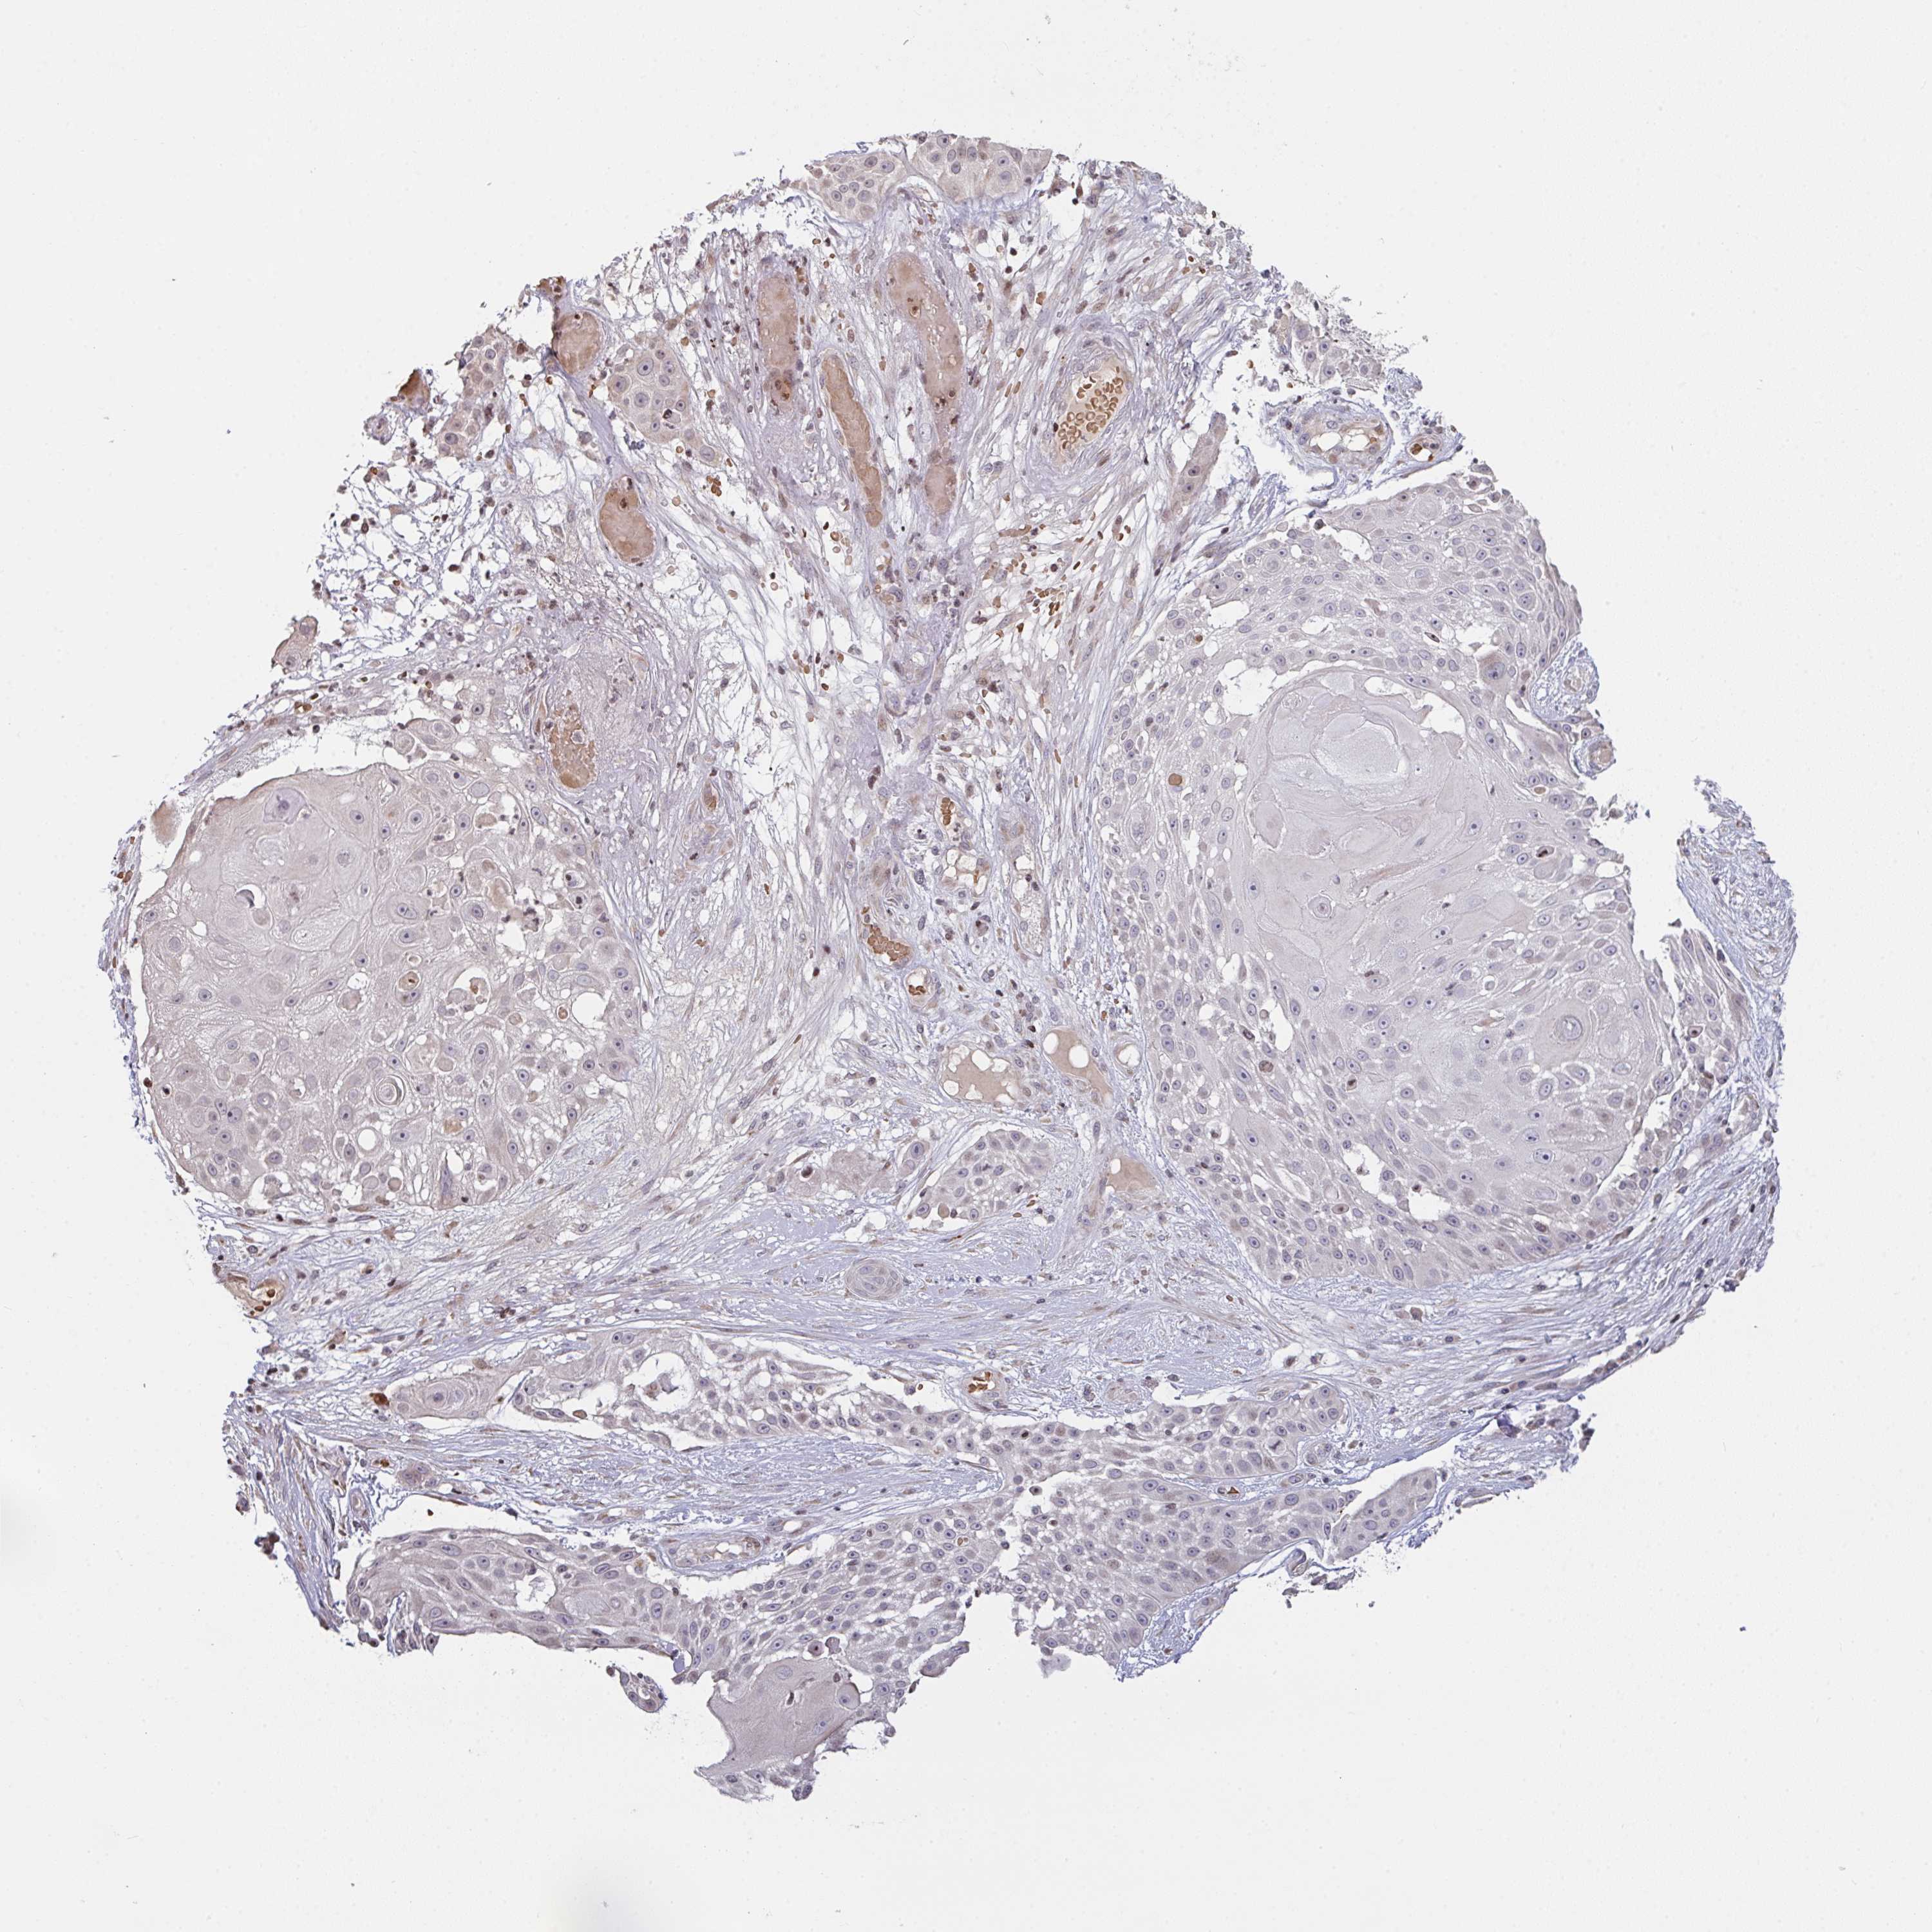

SKIN CANCER - Protein expressioni

A mouse-over function shows sample information and annotation data. Click on an image to view it in a full screen mode. Samples can be filtered based on level of antibody staining by selecting one or several of the following categories: high, medium, low and not detected. The assay and annotation is described here.

Antibody staining in the annotated cell types in the current human tissue is reported as not detected, low, medium, or high, based on conventional immunohistochemistry profiling in selected tissues. This score is based on the combination of the staining intensity and fraction of stained cells.

Each image is clickable and will lead to virtual microscopy that enables deeper exploration of all samples and also displays staining intensity scores, fraction scores and subcellular localization as well as patient and tissue information for each sample.

Antibody HPA057773

Basal cell carcinoma